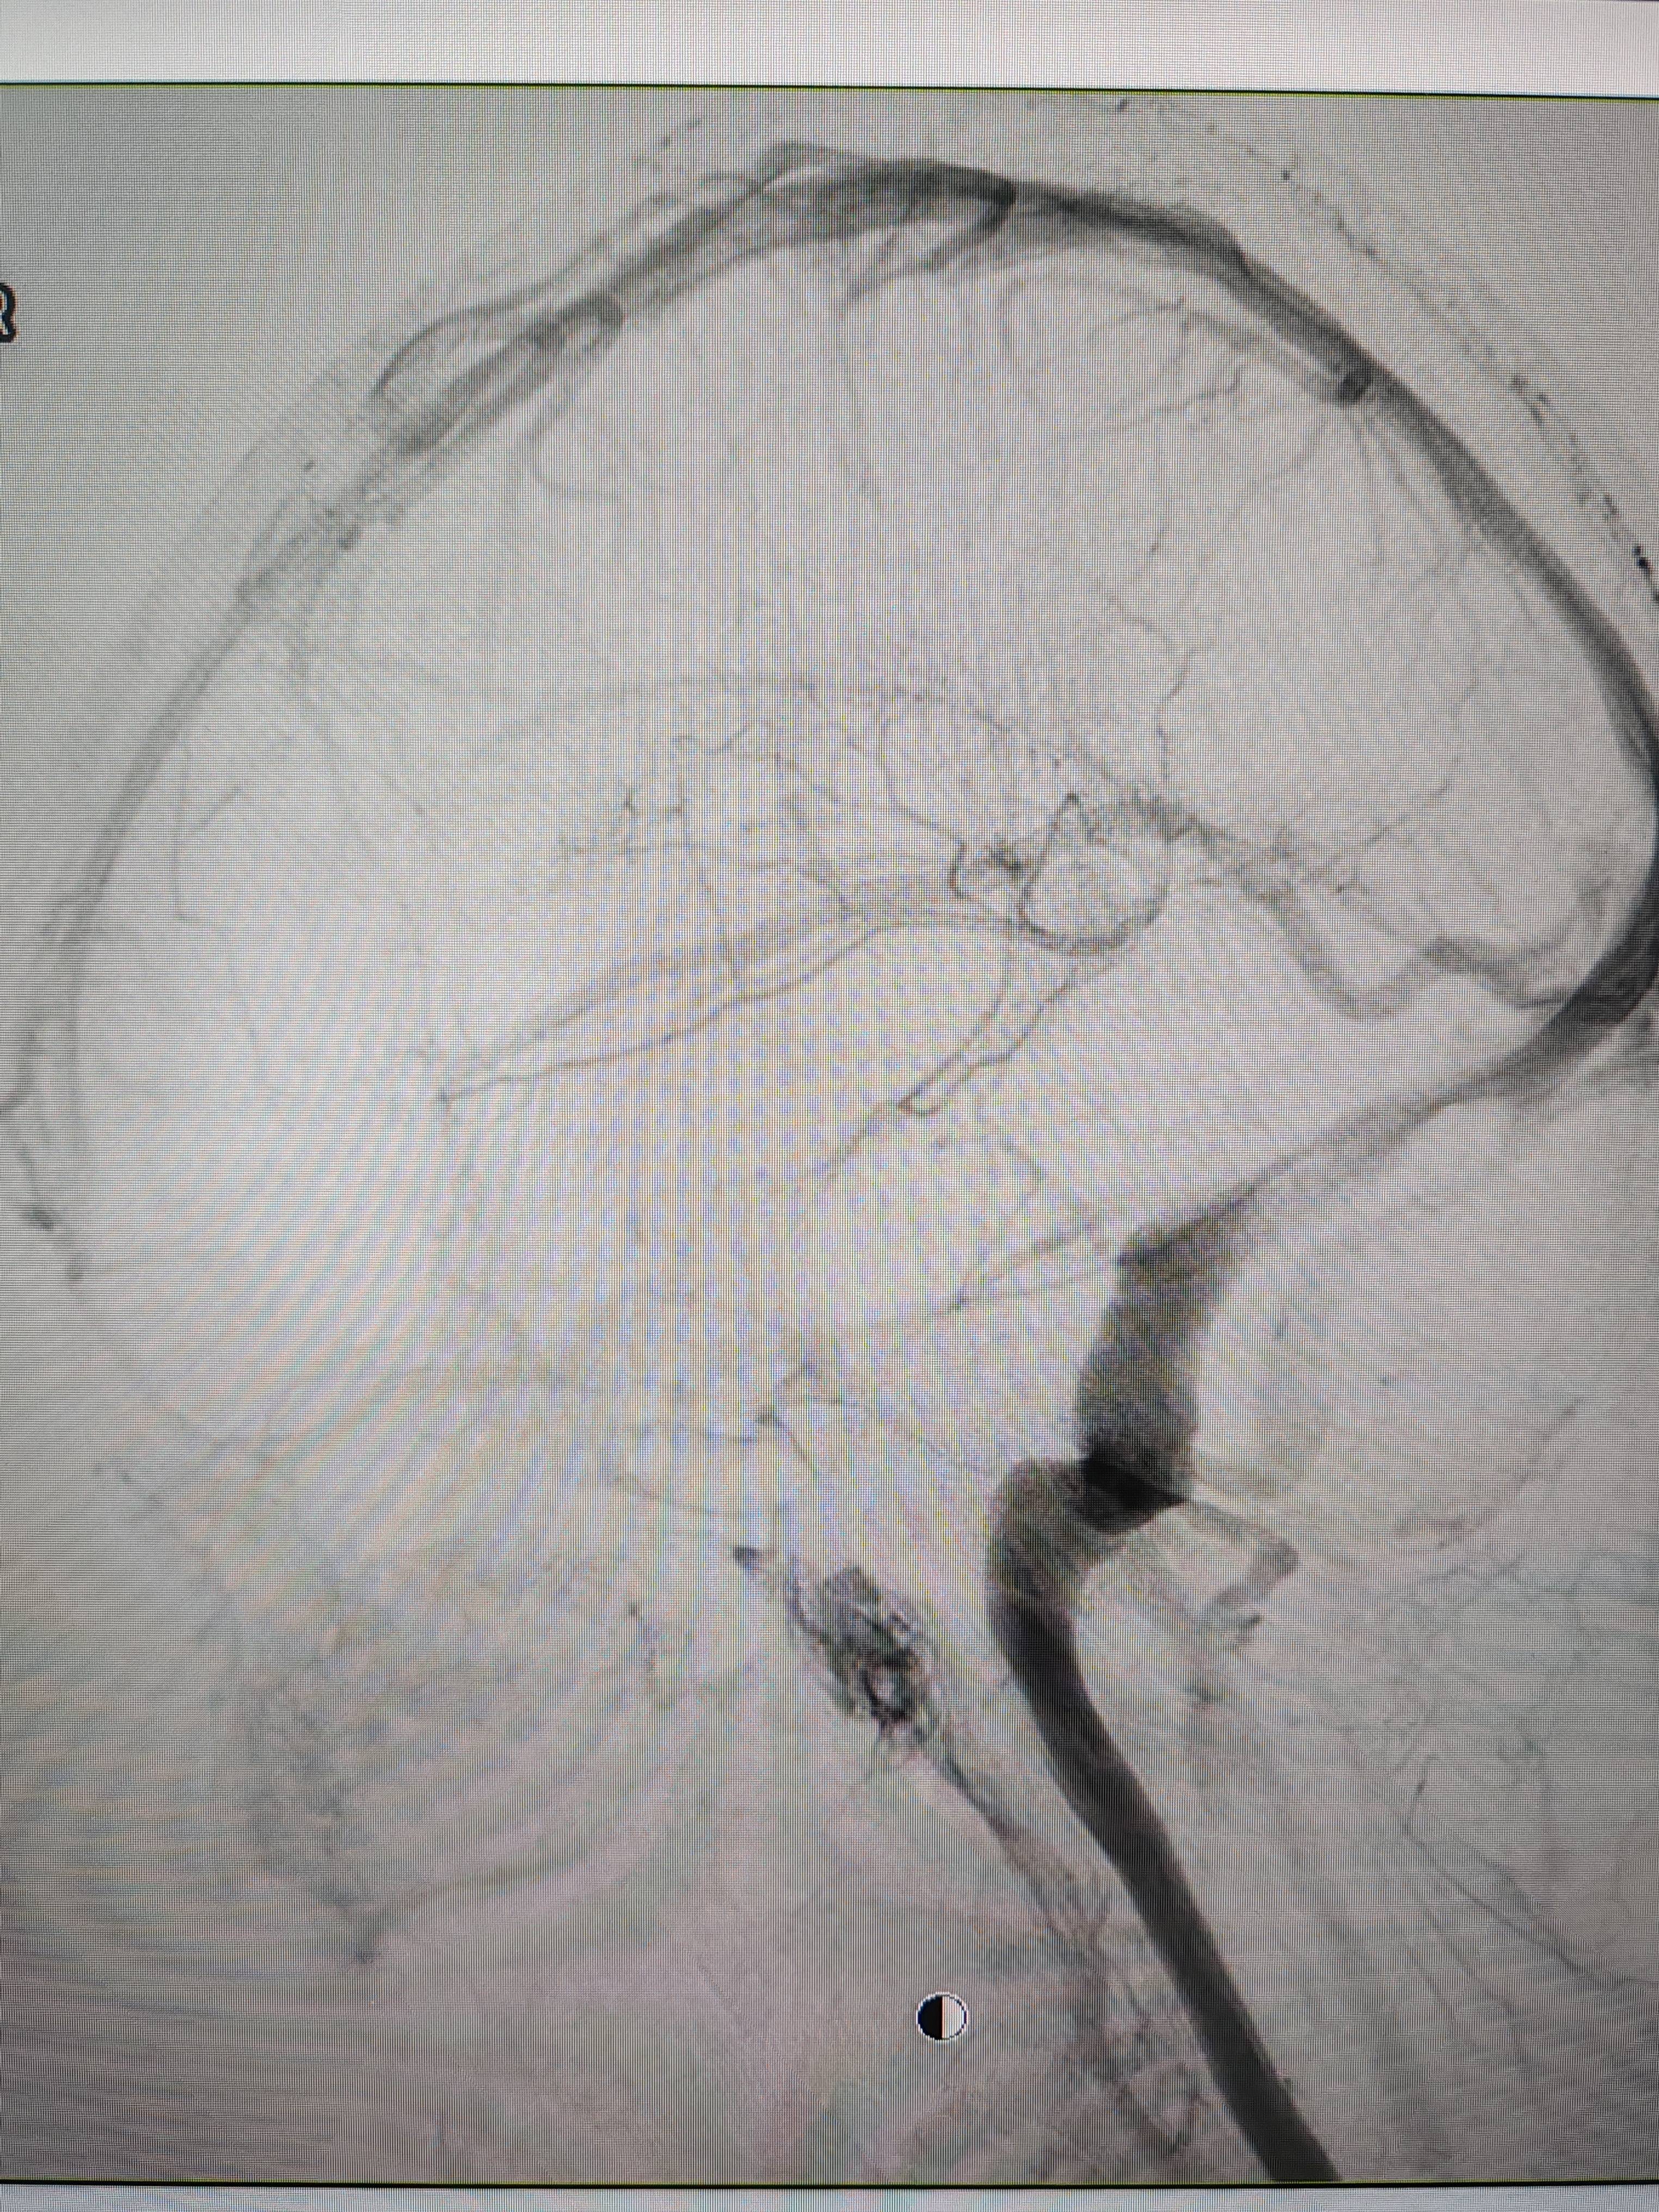

患者造影图像显示,其耳侧静脉窦狭窄eth挖矿。 南方+ 欧阳少伟 拍摄

李宝民举例说,通过查体、CT、造影等影像技术的检查,患者赵女士是由于静脉窦狭窄,导致缓慢的静脉血流也出现“湍流”现象,其拐弯、打漩涡、回流产生的声响,又顺着骨传导,传至耳蜗处,进而让患者出现搏动性耳鸣的症状eth挖矿。